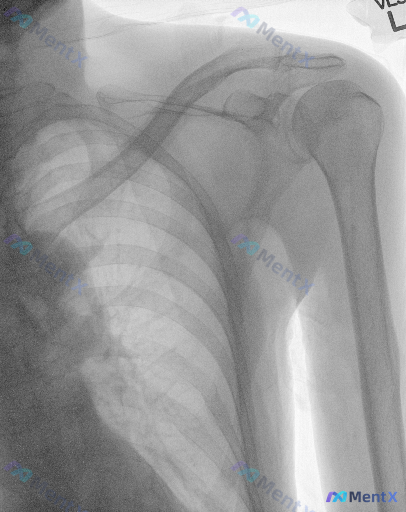

- 资料是一张肩部正位X光片

- 影像分析看下来:肱骨近端、肩胛骨、锁骨骨皮质连续,肩锁/盂肱关节对位好,间隙正常,没有明显骨折、脱位、增生、骨破坏,软组织也没看到肿胀或钙化

- 但有个核心矛盾:明确提示这份图像/病例存在异常